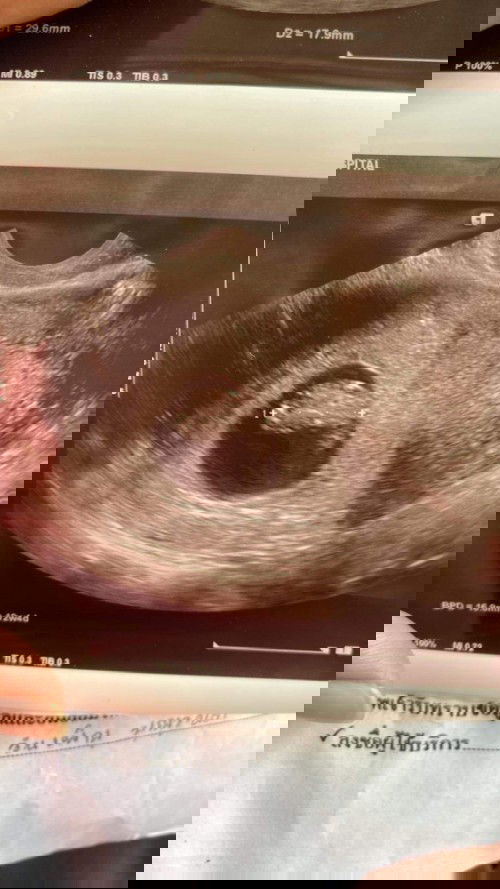

แม่ๆบ้านไหนเป็นแบบนี้บ้างคะ พอดีว่าไปซาวมาแล้วอายุครรภ์ปกติแค่8W แต่ในใบซาวขึ้น12W หมายความว่าไงคะ

#ท้องแรกคะ #ขอบคุณสำหรับคำตอบค่ะ

น้องเป็นเด็ก 8w ที่ตัวเท่าเด็ก 12w ค่ะ